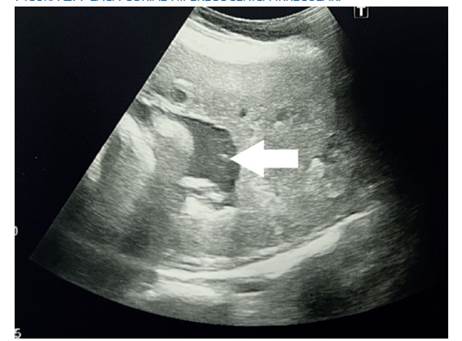

Figura 2 Placa corial hiperecogénica irregular.

Los hallazgos ecográficos más llamativos son la localización anormal de la placenta, hiperecogenicidad y heterogeneidad a la escala de grises en diversas zonas placentarias, parénquima placentario muy diferente al que estamos acostumbrados cuando observamos placentas normoinsertas 17). Por otro lado, se puede evidenciar modificaciones anatómicas de la placa basal y de la placa corial en la ecografía, producto de un proceso neoproliferativo que afecta toda la placenta en forma focal, parcial o total 18). Y la sombra que la acompaña es la presencia de lagunas vasculares de bordes irregulares, que no solamente tienen manifestaciones en la escala de grises sino, más bien, en el flujo aumentado en la placenta al medir con la flujometría Doppler. Estos hallazgos son sugerentes de acretismo 18,19).

La determinación ecográfica de la hiperecogenicidad placentaria heterogénea, placa corial hiperecogénica irregular (aspecto despulido) y la velocidad máxima del flujo Doppler (cm/seg) representan parámetros útiles de aporte al diagnóstico de acretismo placentario.